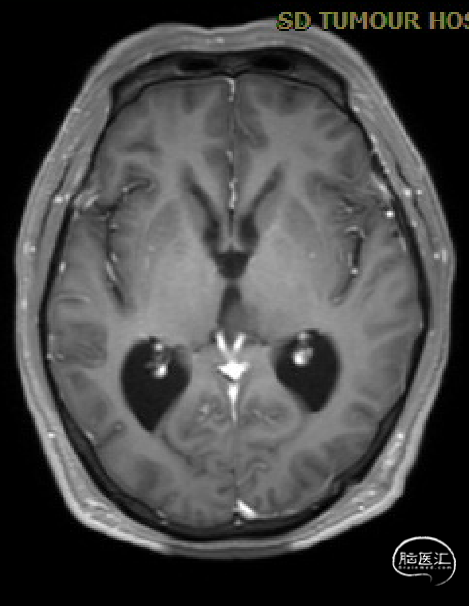

患者5年前无明显诱因出现阵发性头晕,无明显头痛、恶心呕吐等不适,开始未予重视,2022-7-19出现头晕加重,伴视力下降,遂于2022-7-24在当地医院行颅脑MRI提示:松果体区肿瘤伴梗阻性脑积水。

入院检查

初步诊断

松果体区占位,胶质瘤?生殖细胞肿瘤?

脑积水